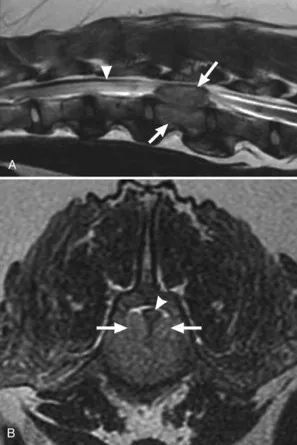

图2 9岁混种犬,2周进行性下肢瘫痪病史,A,腰椎矢状位T2加权MRI。在L2椎骨水平处可见界限清楚的硬膜外病变(长箭头)。病变的骨头,脊髓呈高信号,与水肿一致(短箭头)。B,横断面I2加权MR!显示双侧椎体内静脉从增大(长箭头)。腹侧椎管的正常低信号表示皮质骨明显丧失。眷髓可见背侧偏斜和侧向压缩(短箭头)。在透视引导下获得的L2椎体活检标本的显微镜检查,被诊断为浆细胞肿瘤。